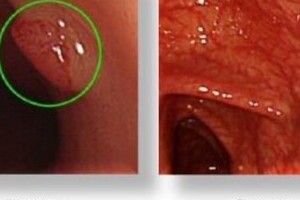

日本発「人工知能でがん発見」技術 大腸がんに乳がん、精度100%に近づく

2017/07/12 08:00